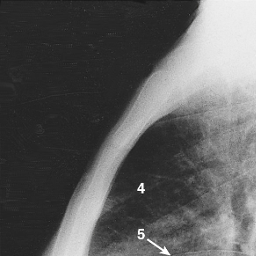

Lateral film. (1,2) Right and left hemidiaphragm;

(3) Gastric air bubble;

(4) Retrosternal space;

(5) Horizontal fissure;

(6) Oblique fissure;

(7) Hila.